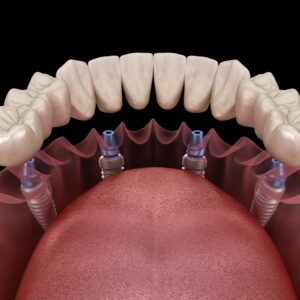

둔산동네비게이션임플란트, 처음이면 알아두어야 할 점은? 안녕하세요. 둔산동네비게이션임플란트 365디지털치과입니다. 치아를 상실한 뒤 임플란트를 고민하게 되는 순간은 대부분 갑작스럽게 찾아옵니다. 갑자기 식사가 불편해지거나, 한쪽으로만 씹게 되는 습관이 생기거나, 시간이 지나면서 주변 치아까지 흔들리는 느낌이 들기도 하는데요. 특히 처음 치료를 고려하는 경우라면 어떤 방식이 나에게 맞는지, 무엇을 기준으로 살펴봐야 하는지 더보기…